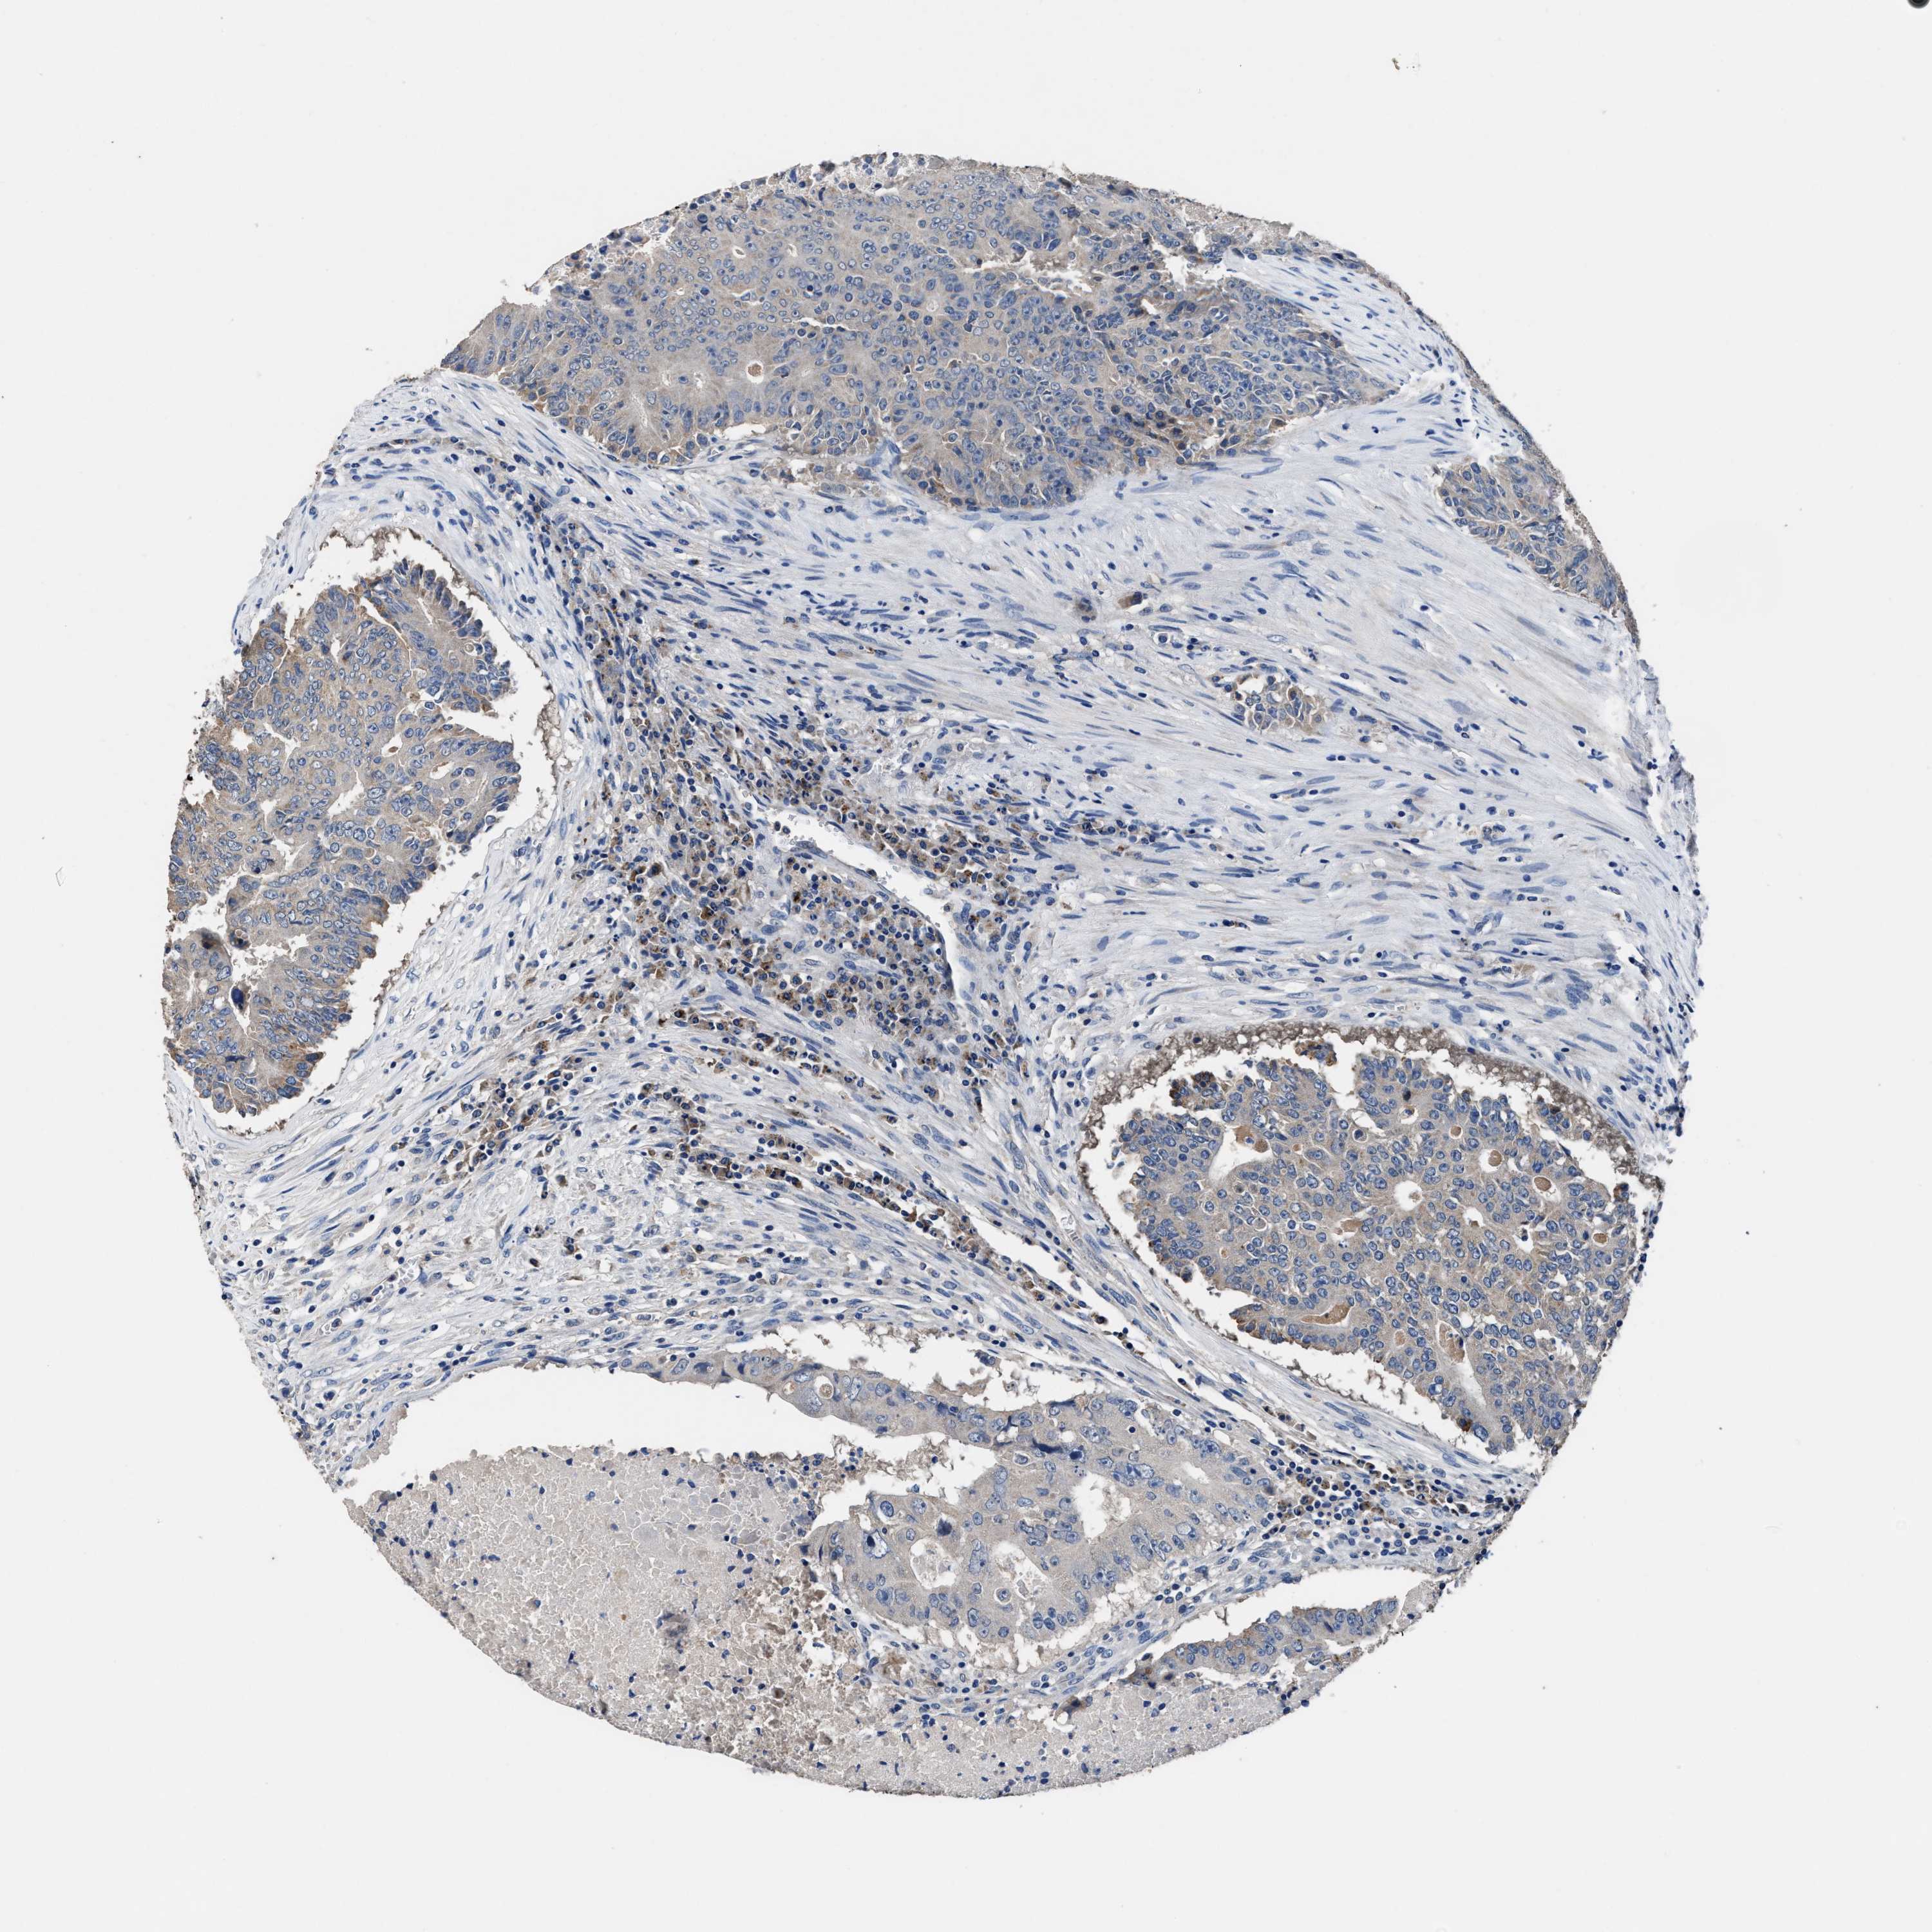

CANCER COLORECTAL CANCER Show tissue menu

Colorectal cancer

Human cancer

Colon adenocarcinoma

Rectum adenocarcinoma